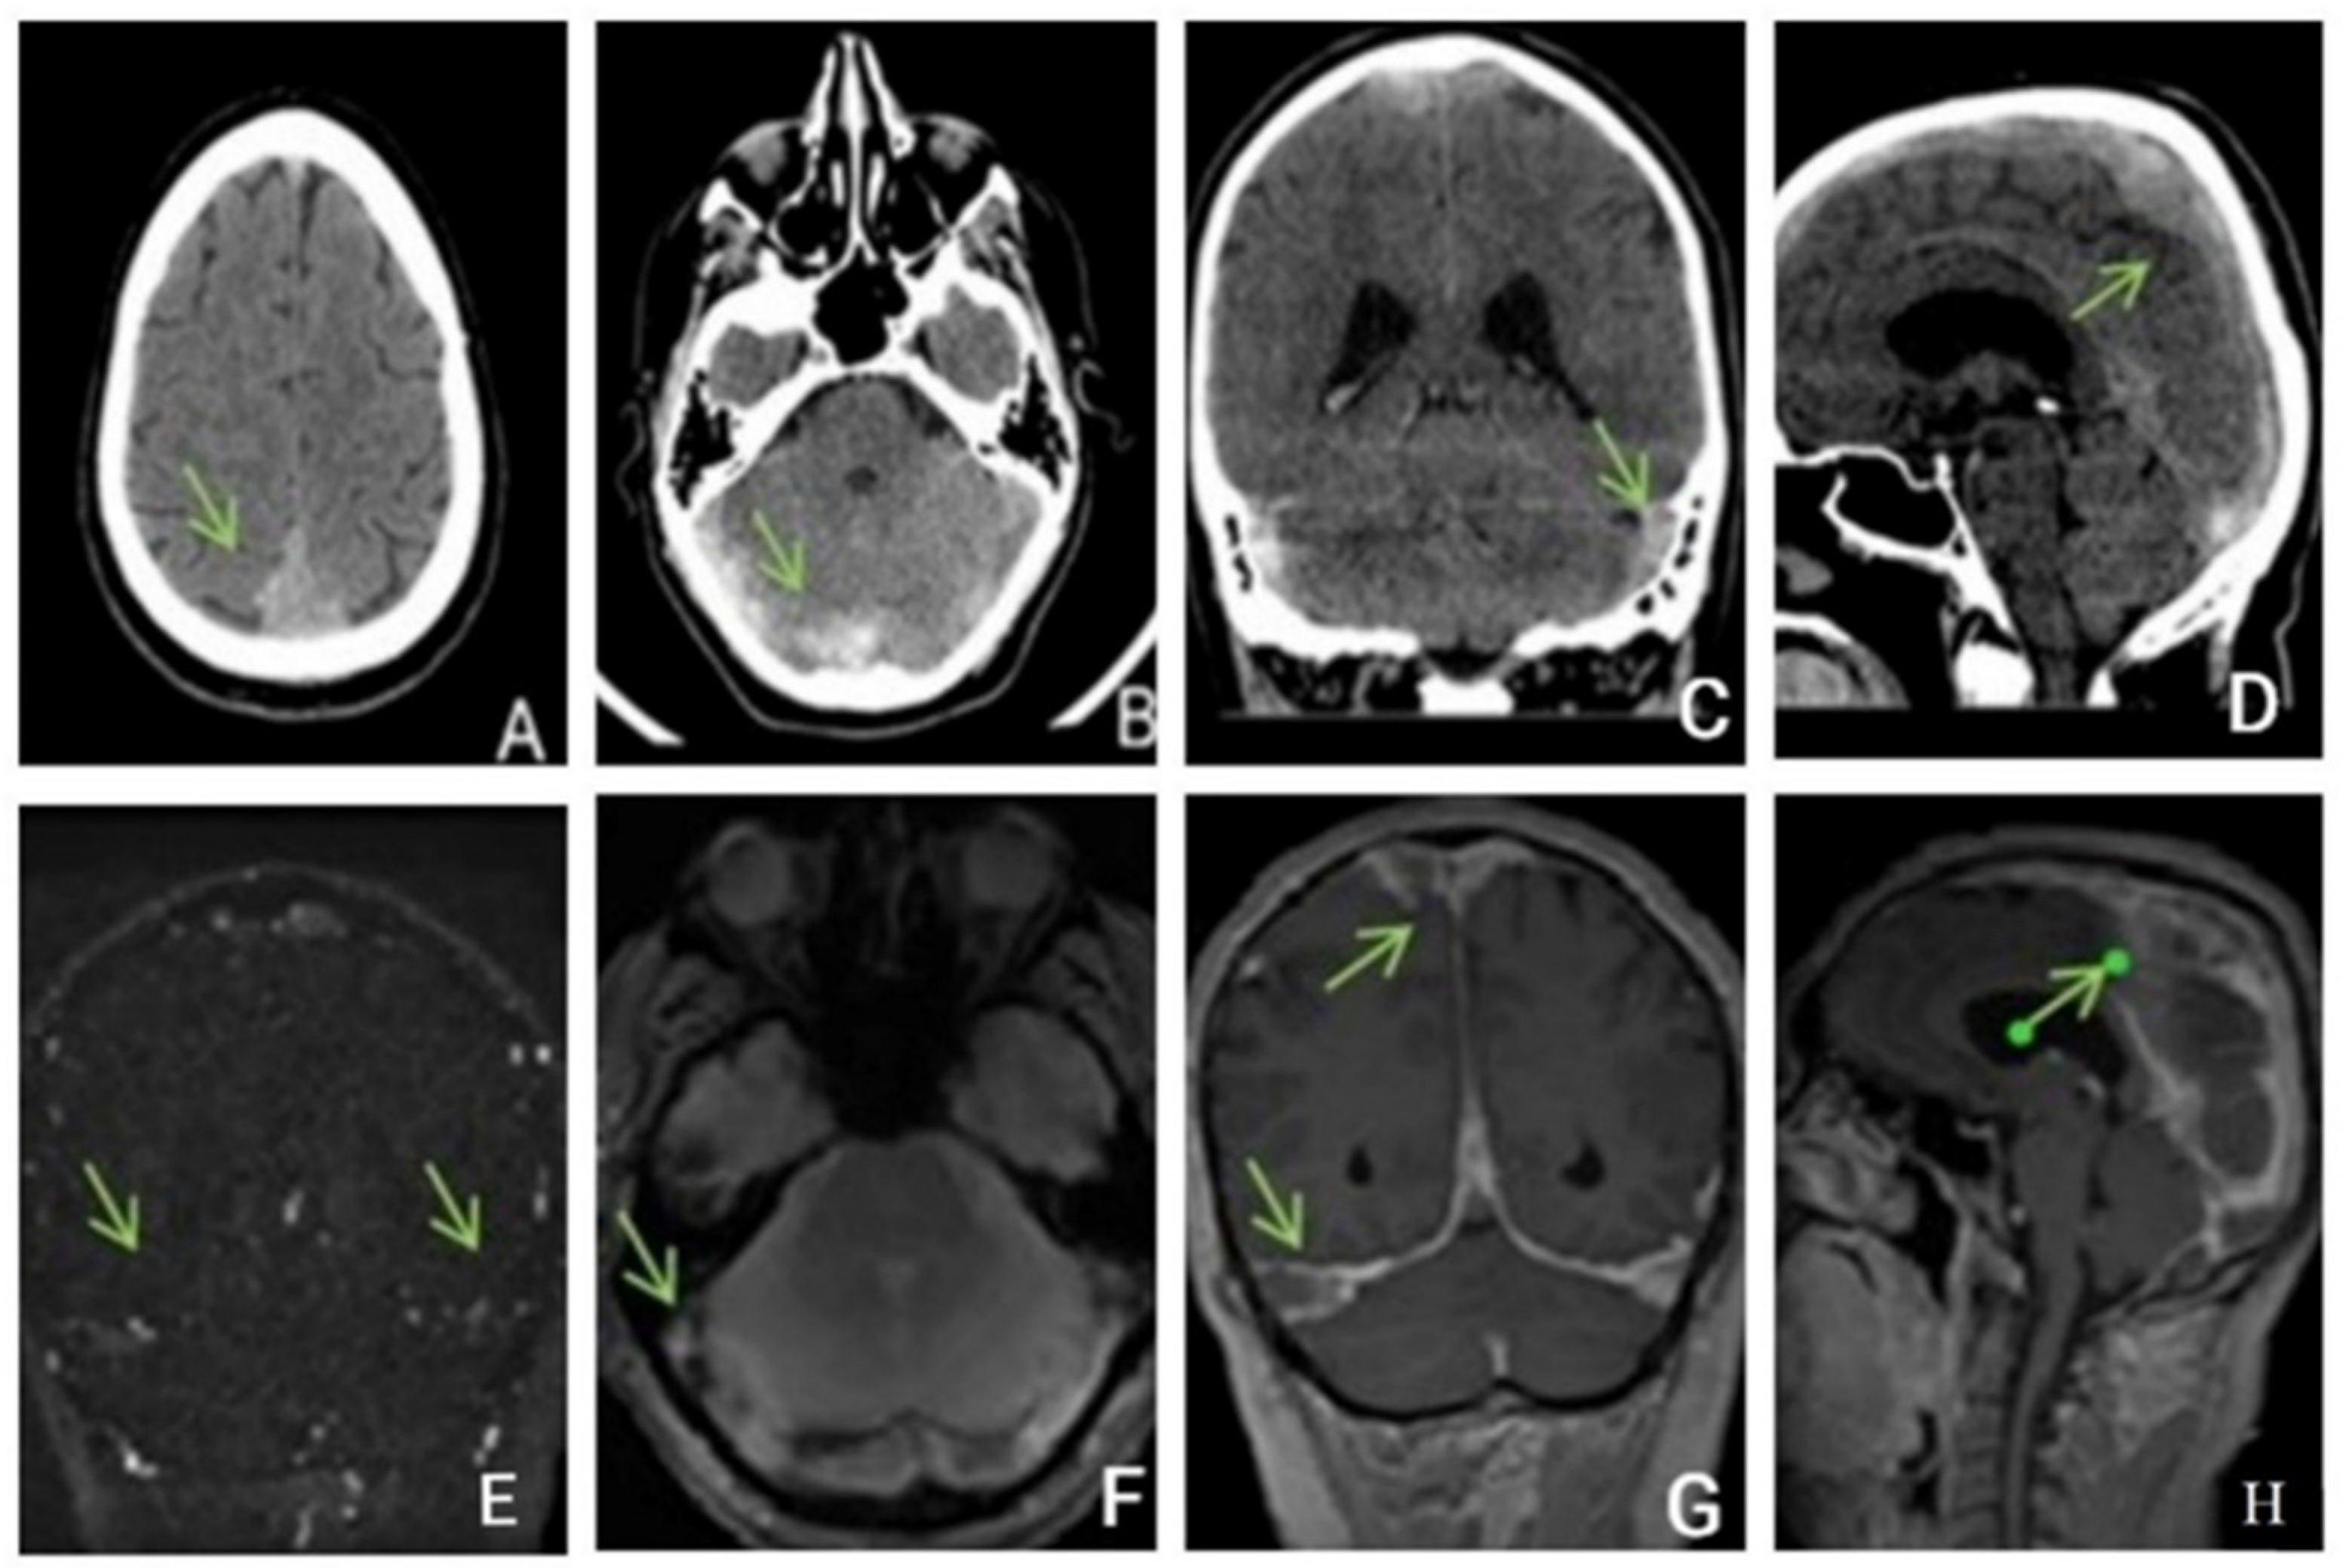

2.3. Case Presentation 3

A 36-year-old, overweight, female patient with medically controlled hypertension as the sole known cardiovascular risk factor came to the emergency department for intense headaches at the level of the right hemicranium, predominantly fronto-orbital, associated with dizziness. The symptoms were refractory to treatment and started three days before presentation. After the debut, the headache significantly progressed in severity, being also accompanied by dizziness, diplopia, mild photophobia, nausea, and inconstant paresthesia in the right limbs, along with a hypertensive spike. The neurological examination identified right external rectus muscle paralysis, mild palpebral edema, and redness at the level of the eyeballs, predominantly on the right side, alongside dysarthria. The patient complained of diplopia on frontal and bilateral horizontal gaze. Otherwise, the exam was unremarkable, without fever. The contrast CT Head performed was found to be normal.

A brain MRI (Figure 5) showed flow asymmetry at the level of the cavernous sinuses, left more than right, coupled with fluid accumulation in the left mastoid cells, whilst cerebral parenchyma had morphology and signals within normal limits, thus establishing the diagnosis of bilateral (left > right) cavernous sinus thrombosis. The patient was started on continuous heparin infusion followed by treatment with acenocoumarol.

Figure 5.

Non-enhanced MRI (at onset): ((A)—T2 axial, (B)—T1 sagittal, (C)—T2* axial, (D)—venous TOF coronal) shows unremarkable parenchyma and absence of flow in cavernous sinuses on TOF imagesFive months later, the patient came back to our clinic complaining of paroxysmal episodes of altered state of consciousness with language disorders such as verbal barrage followed by disorientation. An EEG was performed, showing a low-voltage background path, weakly modulated in spindles in the left derivations, reactive when opening the eyes, and rare isolated degraded peak-wave complexes, thus concluding that the patient was experiencing focal onset impaired awareness seizures; she was then started on antiepileptic treatment with oxcarbazepine 300 mg twice daily. She also was psychiatrically examined due to emotional lability confirming the diagnosis of depression and allowing antidepressant treatment to be started.

The six-month follow-up MRI identified persistent left maxillary sinusitis and cavernous sinus asymmetry but with an improved flow in the left one. Additionally, after 2 weeks of subcutaneous low-weight heparin, the panel for thrombophilia was requested and a protein C and S deficit was found, with the other tests (lupus anticoagulant, antithrombin III, factor V Leiden, IgM and IgG antiphospholipid antibodies, IgM and IgG anti-cardiolipin antibodies, IgM and IgG anti beta-2 glycoprotein I, p-ANCA, and c-ANCA) being within normal values. Thus, thrombophilia was diagnosed and the indication of lifelong anticoagulation established.

In the following days, the patient′s condition continued to worsen. She did not respond to nociceptive stimuli, spontaneously mobilized her limbs, and had involuntary movements of the jaw. Considering the unfavorable and unpredictable evolution, in agreement with the family, we decided to perform therapeutic abortion. A new brain CT was performed (Figure 7).

Figure 7.

CT without contrast (A–C) and with (D–F) contrast enhancement shows hyperdensities in the Galen vein and internal cerebral veins with nonhomogeneous thalamic nuclei. After contrast enhancement, there was a slight enhancement in the veins and hypoperfusion of the thalamic nuclei.